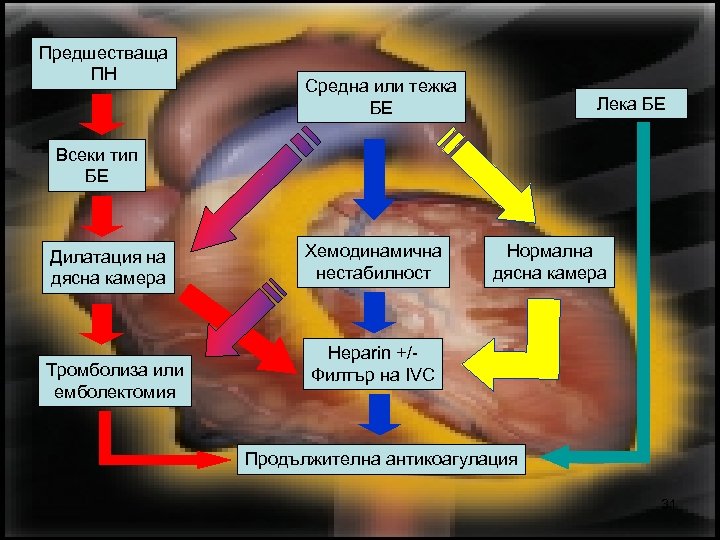

Предшестваща ПН Средна или тежка БЕ Лека БЕ Всеки тип БЕ Дилатация на дясна камера Тромболиза или емболектомия Хемодинамична нестабилност Нормална дясна камера Heparin +/Филтър на IVC Продължителна антикоагулация 31